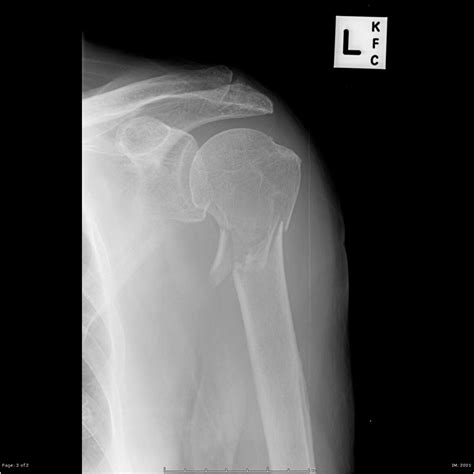

Diagnosing Proximal Humerus Fractures

Diagnosing a proximal humerus fracture involves a combination of physical examination and imaging tests. The diagnostic process typically includes:

• Imaging Tests: X-rays are the primary imaging tool used to diagnose proximal humerus fractures. In some cases, additional tests such as CT scans or MRIs may be ordered to provide more detailed images.

Classification of Proximal Humerus Fractures

Proximal humerus fractures are classified based on the location and pattern of the fracture. The most common classification systems include:

• Neer Classification: This system categorizes fractures based on the number of parts involved (one, two, three, or four parts).

• AO/OTA Classification: This system uses a more detailed coding system to describe the fracture pattern and severity.